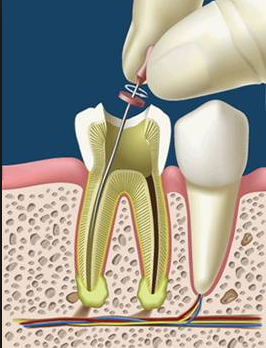

La terapia endodóntica consiste en la extirpación total de lapulpa dental (nervio-arteria-vena) Se aplica en piezas dentales fracturadas, con caries profundas o lesionadas en su tejido pulpar.

Y el estudio de la Patología Periapical Esta es irreversible y la única opción terapéutica es la extirpación total de la pulpa dental, y la obturación tridimensional del conducto dentario.